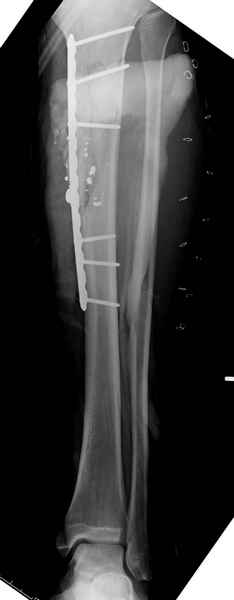

Здесь несколько примеров из нашей практики:

1 неполный перелом большеберцовой кости перкутанная пластина